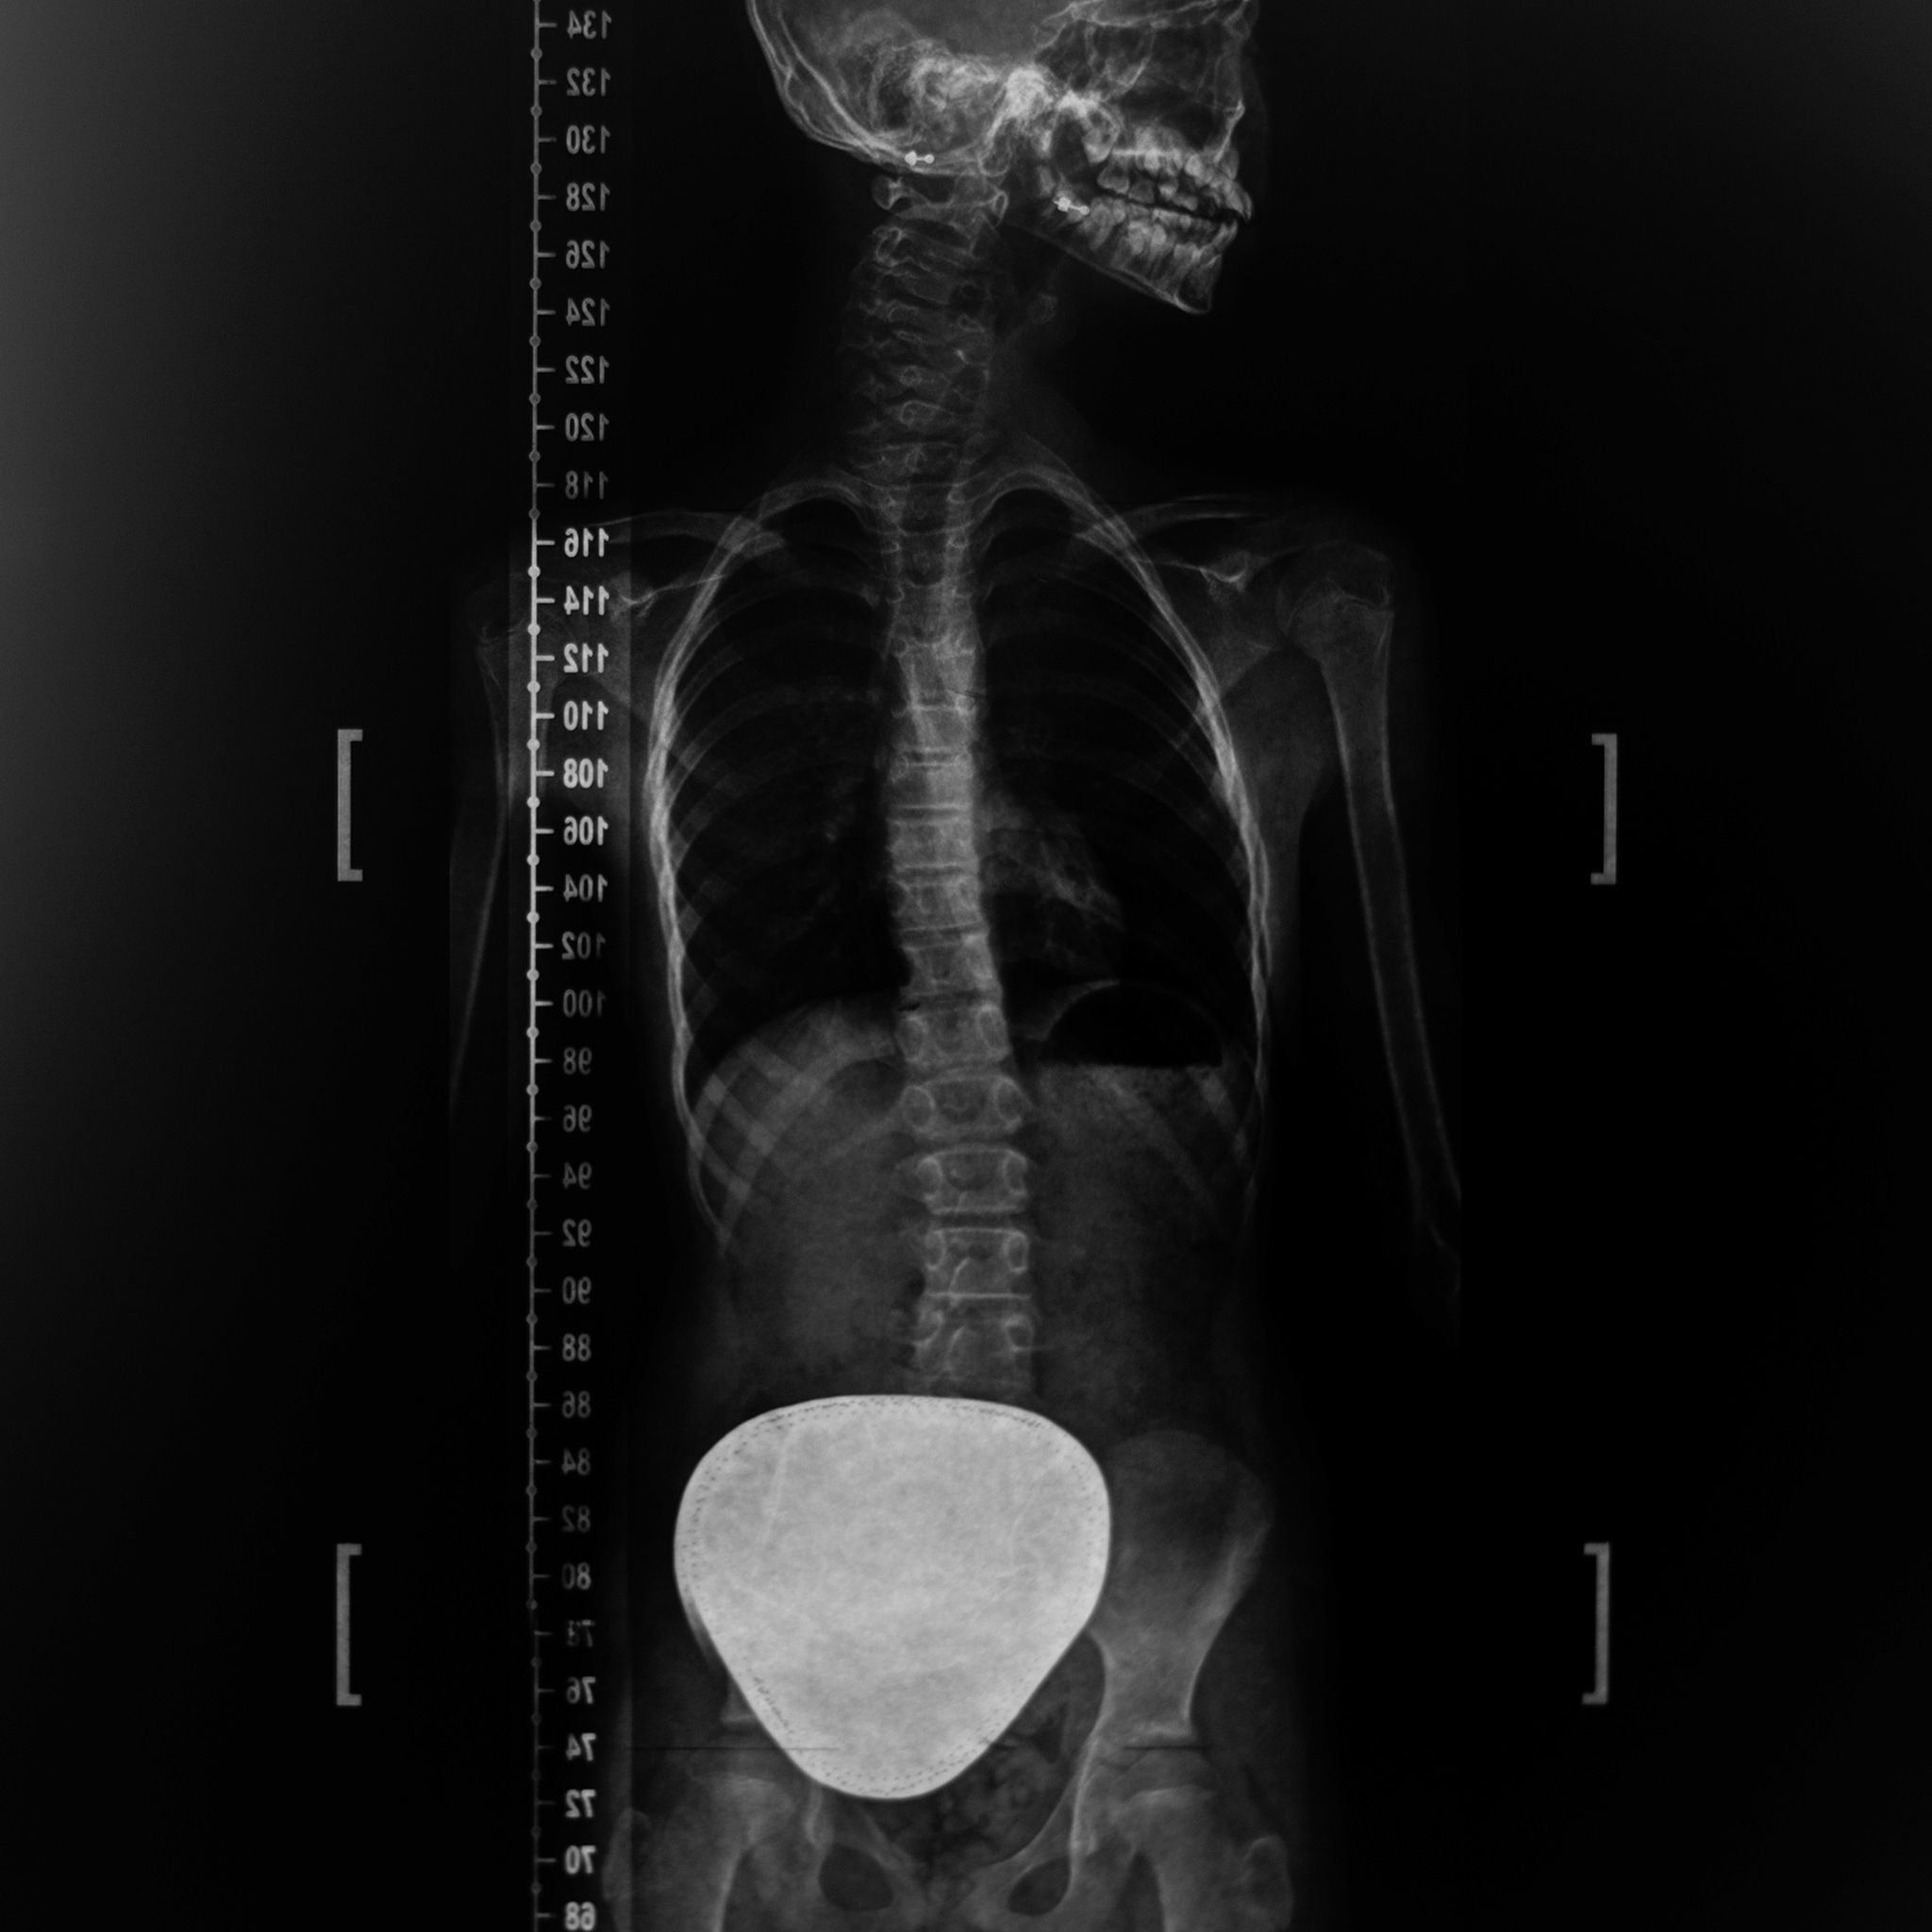

Back Brace